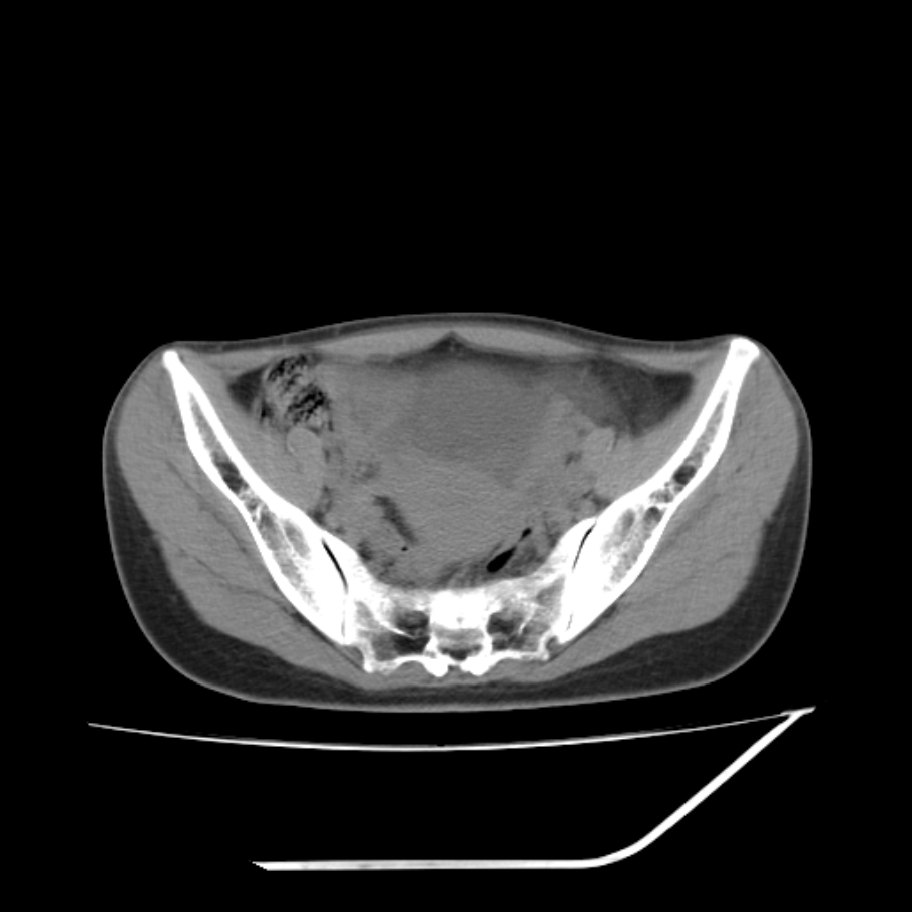

女,25岁。偶尔有右下腹不适感,余无明显异常。(结婚半年),囊壁较厚,是卵巢囊肿吗?

其上一层面见两枚小气泡影,考虑为肠管影可能,不完全除外囊肿

右侧卵巢区椭圆形囊性肿物,内壁光滑 无分隔。直肠子宫间隙内有少量积液征象。结合临床考虑卵巢巧克力囊肿,还要问问有没有痛经,本例ct怎么没有灌肠?要是灌肠或前一前口服造影剂,起码可以和肠管区别开

b超示:囊实性占位,畸胎瘤?临床有痛经。

考虑右侧卵巢囊性占位性病变(巧克力囊肿?),盆腔积液有不排除宫外孕可能,请结合临床和b超。

右侧卵巢囊伴盆腔少量积液。